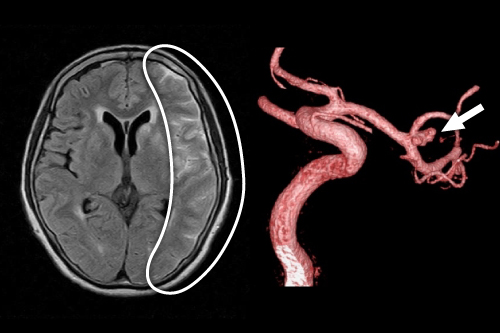

可逆性脳血管攣縮症候群(RCVS)による頭痛

可逆性脳血管攣縮症候群(RCVS)は少なくとも半数は二次性であり、主に産褥後、あるいは薬剤性におこることがあります。頭部MRIで30~80%の症例で異常を呈することがあるとされており、頭蓋内出血(円蓋部くも膜下出血、脳内出血など)脳梗塞、後部可逆性脳症症候群(PRES)に一致する脳浮腫を認める場合があります。